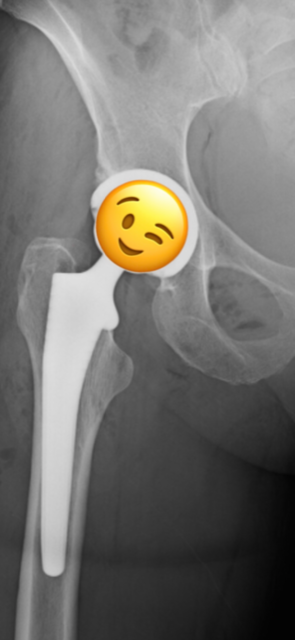

About eight months ago I started to experience pain in the right hip so I went back to see Rob for more PT. After weeks of not much improvement, he suggested I see Dr. Moley, get new images and see what he could do. Dr. Moley fit me in quickly - on 1.25.21 (he's the best) - and upon examination, he was emphatic that it was time for a hip replacement. He told me he was surprised I'd lasted this long! I left with the recommendation to see Dr. Su for surgery (Rob Fay also recommended him and he'd replaced my mom's hip 5 years earlier). I saw Dr. Su on February 3rd and scheduled surgery for the first available time which was February 22nd.

I requested the first appointment and so by 9:30am, I was in recovery! The nurses were kind and understanding of my fear of IVs, and Dr. Kay, my anesthesiologist, worked his magic so there was no burning from the initial anesthesia! Everyone at the hospital was helpful and accommodating as well. And now for the best part! I was off cane in less than 3 weeks, walking over 2 miles. I was able to be on my Peloton (without much tension) within a week - and could ride for 60 minutes! At 3 and a half weeks, I was back working out with my trainer, now able to do squats, lunges, etc.! It's now been just over 5 weeks. I spent a week in Telluride, CO walking around 5 miles a day, including some hiking. I NEVER experienced any pain due to the surgery. A little discomfort and soreness, but NO PAIN! NONE!! It's like I never had surgery! And the incision is small and horizontal - near the bikini line too! I will have to have my left hip replaced as well, once I experience pain (x-rays make it clear). I won't be worried or anxious next time, thanks to Dr. Su and his team!